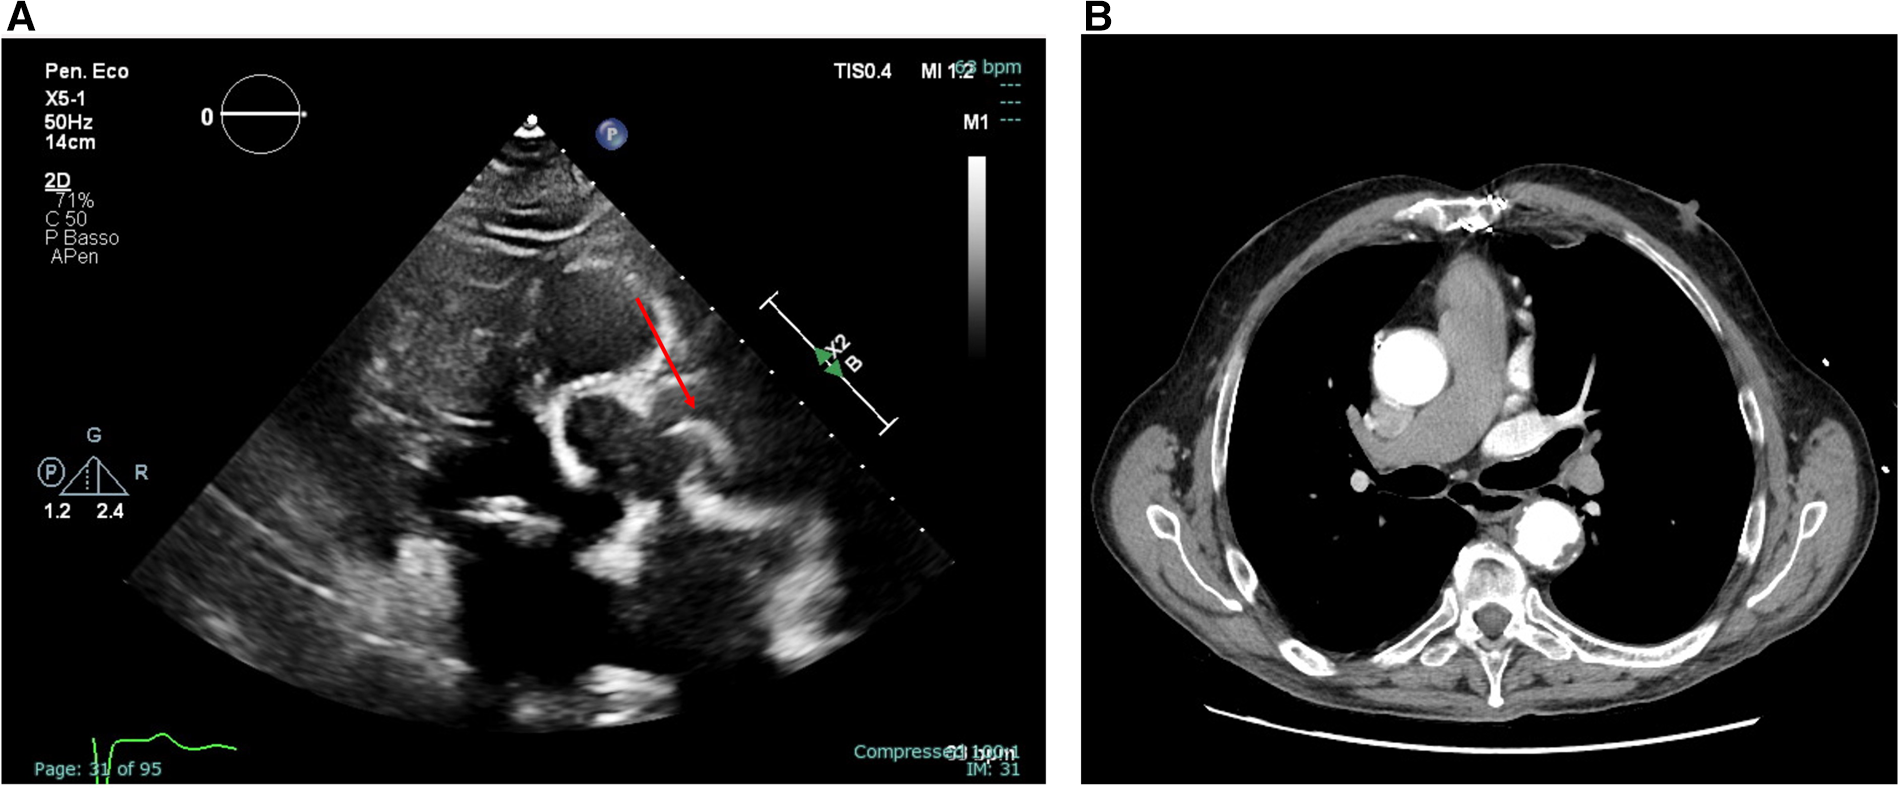

The transthoracic echocardiogram revealed an extremely mobile, strip-shaped filamentous mass at the aortic root level above the sino-tubular junction, apparently attached to the aortic wall (Figure 1A- left panel; Supplementary Video S1). The aortic root and ascending aorta were of normal size, and no echocardiographic signs of aortic dissection were present. The exam revealed mild calcification of the aortic valve cusps, accompanied by moderate valvular stenosis. A mildly dilated left ventricle with concentric remodeling and moderately reduced left ventricular ejection fraction was also detected.

Figure 1

Transthoracic echocardiography (parasternal long-axis view) showing an extremely mobile, strip-shaped filamentous mass located at the level of the sino-tubular junction [(A), left panel, still frame of Supplementary Video S1] and axial view of a thoracic CT angiography not detecting the highly mobile and thin mass [(B), right panel].

The mass was incidentally found, and the patients denied symptoms possibly related to this finding. However, to exclude possible intimal flap or other acute aortic diseases, the patient was admitted for urgent Cardiac Tomography (CT) angiography, which excluded aortic dissection. Notably, the mass visualized on transthoracic echocardiography was not detectable on CT, despite a thorough review of both contrast-enhanced and non-contrast images (Figure 1B- right panel). As this was a non-gated angiographic CT scan, its sensitivity for detecting small, mobile intraluminal structures was likely limited by motion artefacts and the absence of synchronized acquisition. Indeed, this mass was visualized consistently across multiple echocardiographic windows and probes, ruling out potential artifacts. Blood cultures and laboratory inflammation indices were also negative. Moreover, given the location of the attachment and the morphological characteristics, it was unlikely that the mass represented a lesion of another nature (e.g., Lambl's excrescence or papillary fibroelastoma of the aortic valve).